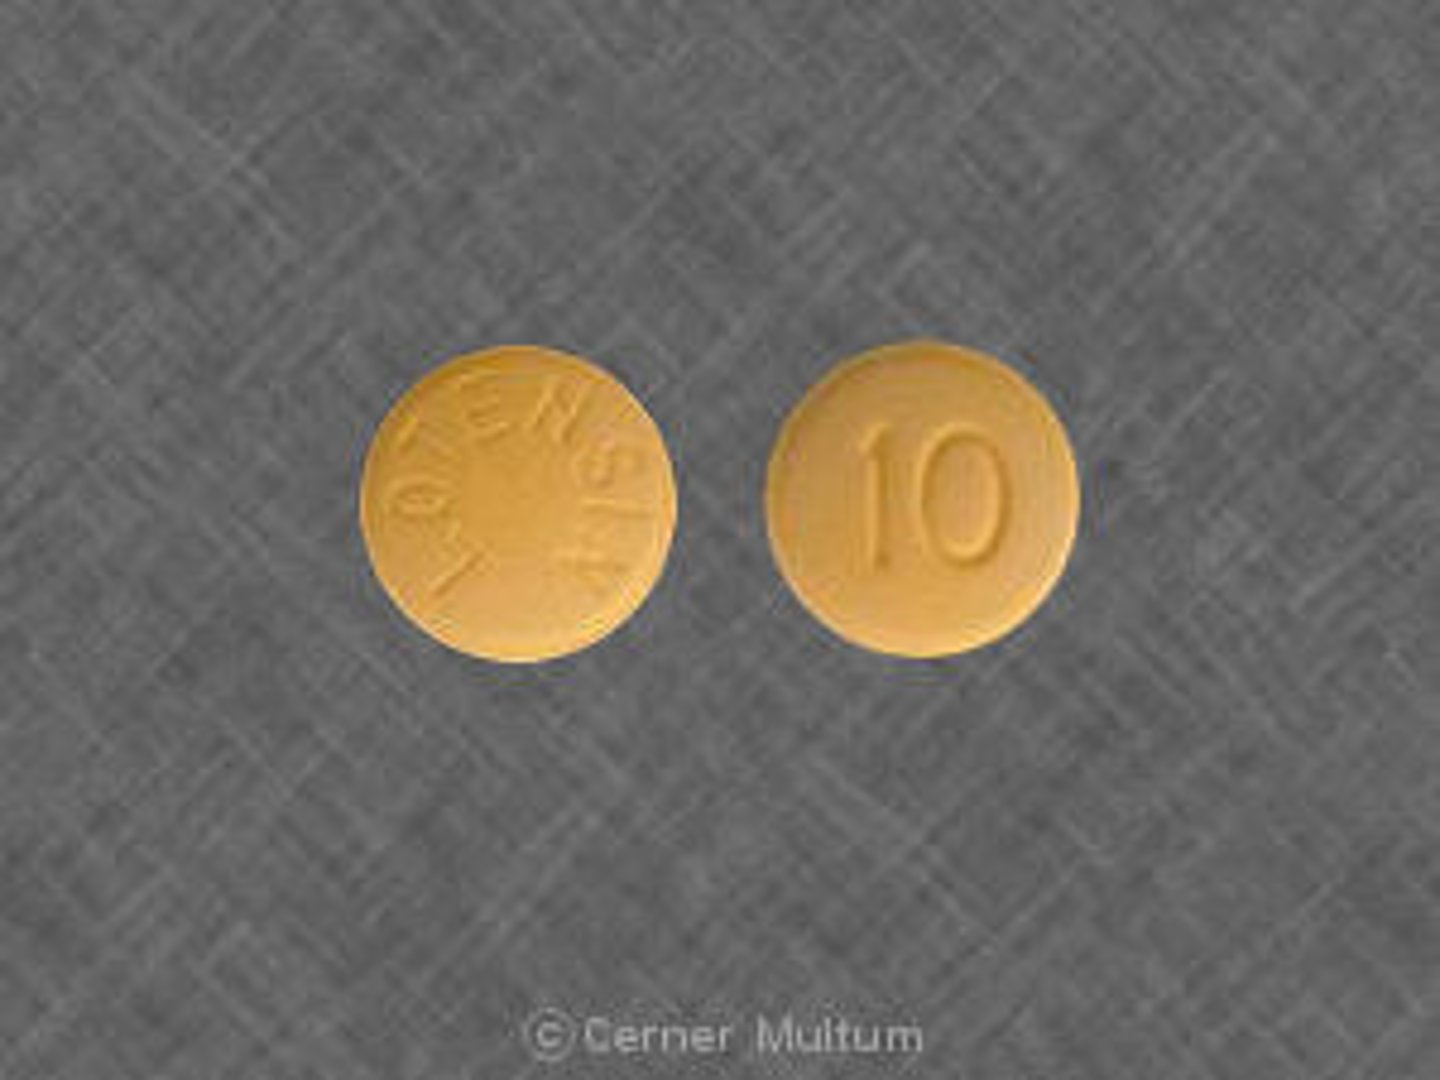

Benazepril

Brand: Lotensin

Class: ACEi

Contraindication: Pregnancy Category D

Indication: Antihypertensive

Schedule: NCLM